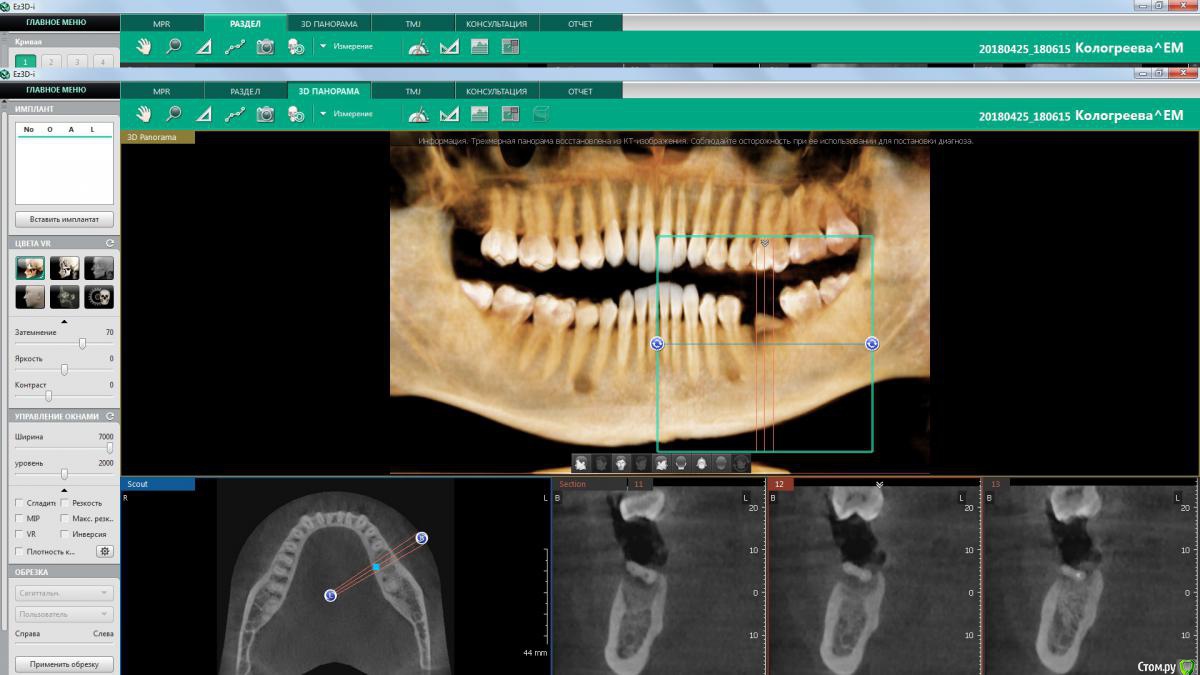

колесников Опубликовано 10 августа, 2018 Поделиться Опубликовано 10 августа, 2018 (изменено) Ещё один случай. Время ожидания 3-4мес. Одну ногу как говорится побрил,а другую оставил обрастать. Пробка только на 36ом. В лунках графт. У 37 более выражен лизис стенок альвеолы, и это всего за 3 мес. У 36ого, как водится, анатомический контур десны Изменено 10 августа, 2018 пользователем колесников 5 Ссылка на комментарий